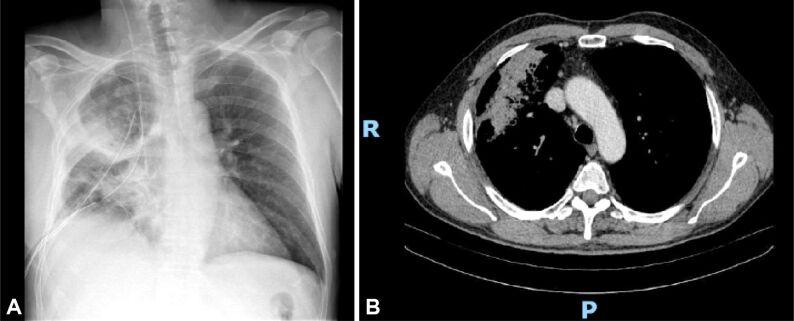

The most challenging cases encountered during the recent years were those of lung hamartoma associated with eosinophilic pneumonia because of the multicentricity of the disease and the suspicion for metastasis in the clinical setting, pulmonary aspergillosis that presented as a cystic lesion with a 9 mm mural nodule, actinomycosis discovered as firm nodule showing aspects of false pleural invasion, cryptococcosis - a hilar mass for which a pneumectomy was prepared, pulmonary parasitosis that presented as a nodule with irregular borders, causing pleural retraction, one case of inflammatory myofibroblastic tumor of the lung, one case of tumorlet type neuroendocrine lesion in a patient with history of melanoma and renal oncocytoma, admitted under the suspicion of lung metastasis.

近年来遇到的最具挑战性的病例是肺错构瘤伴嗜酸性肺炎,因为疾病的多中心性和临床环境中对转移的怀疑,表现为囊性病变伴 9 毫米壁结节的肺曲霉病,表现为假性胸膜侵犯特征的坚实结节的放线菌病,准备进行肺切除术的隐球菌病 - 肺门肿块,表现为不规则边界结节导致胸膜回缩的肺寄生虫病,一例肺部炎性肌纤维母细胞瘤,一例黑色素瘤和肾嗜酸细胞瘤病史患者的肿瘤样神经内分泌病变,怀疑为肺癌转移而入院。